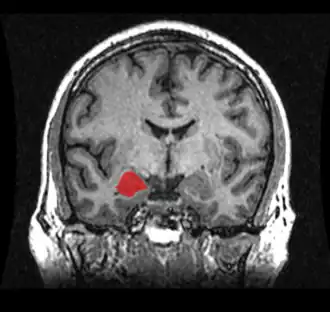

Figure 3. Location of the amygdala.

The amygdala is an almond-shaped cell mass, located in the temporal cortex. It is made up of different groups of cells, called the lateral, basal and accessory basal nuclei – collectively called the basolateral amygdala. Structures surrounding the basolateral amygdala, including the central, medial and cortical nuclei are traditionally called the ‘amydaloid complex’, and together with the basolateral amygdala are collectively called ‘the amygdala’ (Davis & Whalen, 2000). The amygdala is associated with fear and emotional significance of a stimulus (Burton, Westen, Kowalski, & Westen, 2015). Stimulation of the amygdala is associated with autonomic reactions such as the ‘fight or flight’ response, increasing heart rate and blood pressure (Thomas, 2001). A study into lesions of the amygdaloid complex of monkeys in 1956 showed that the lesions on the amygdala diminished the monkey’s normal fear response (Weiskrantz, 1956). Studies indicate that increased amygdala volume may be correlated with increased amygdala reactivity (Cohodes & Gee, 2017). Studies have found that children and adolescents with anxiety related disorders show larger amygdala volumes (Milham & Banich, 2005), and another study in 2010 by Tottenham et al., found that increased amygdala volume predicted symptoms of anxiety in post-institutionalised children. Another study showed that children with anxiety disorders showed exaggerated amygdala responses to fearful faces compared to healthy children, suggesting that the amygdala function is affected by anxiety related disorders (Thomas, 2001).